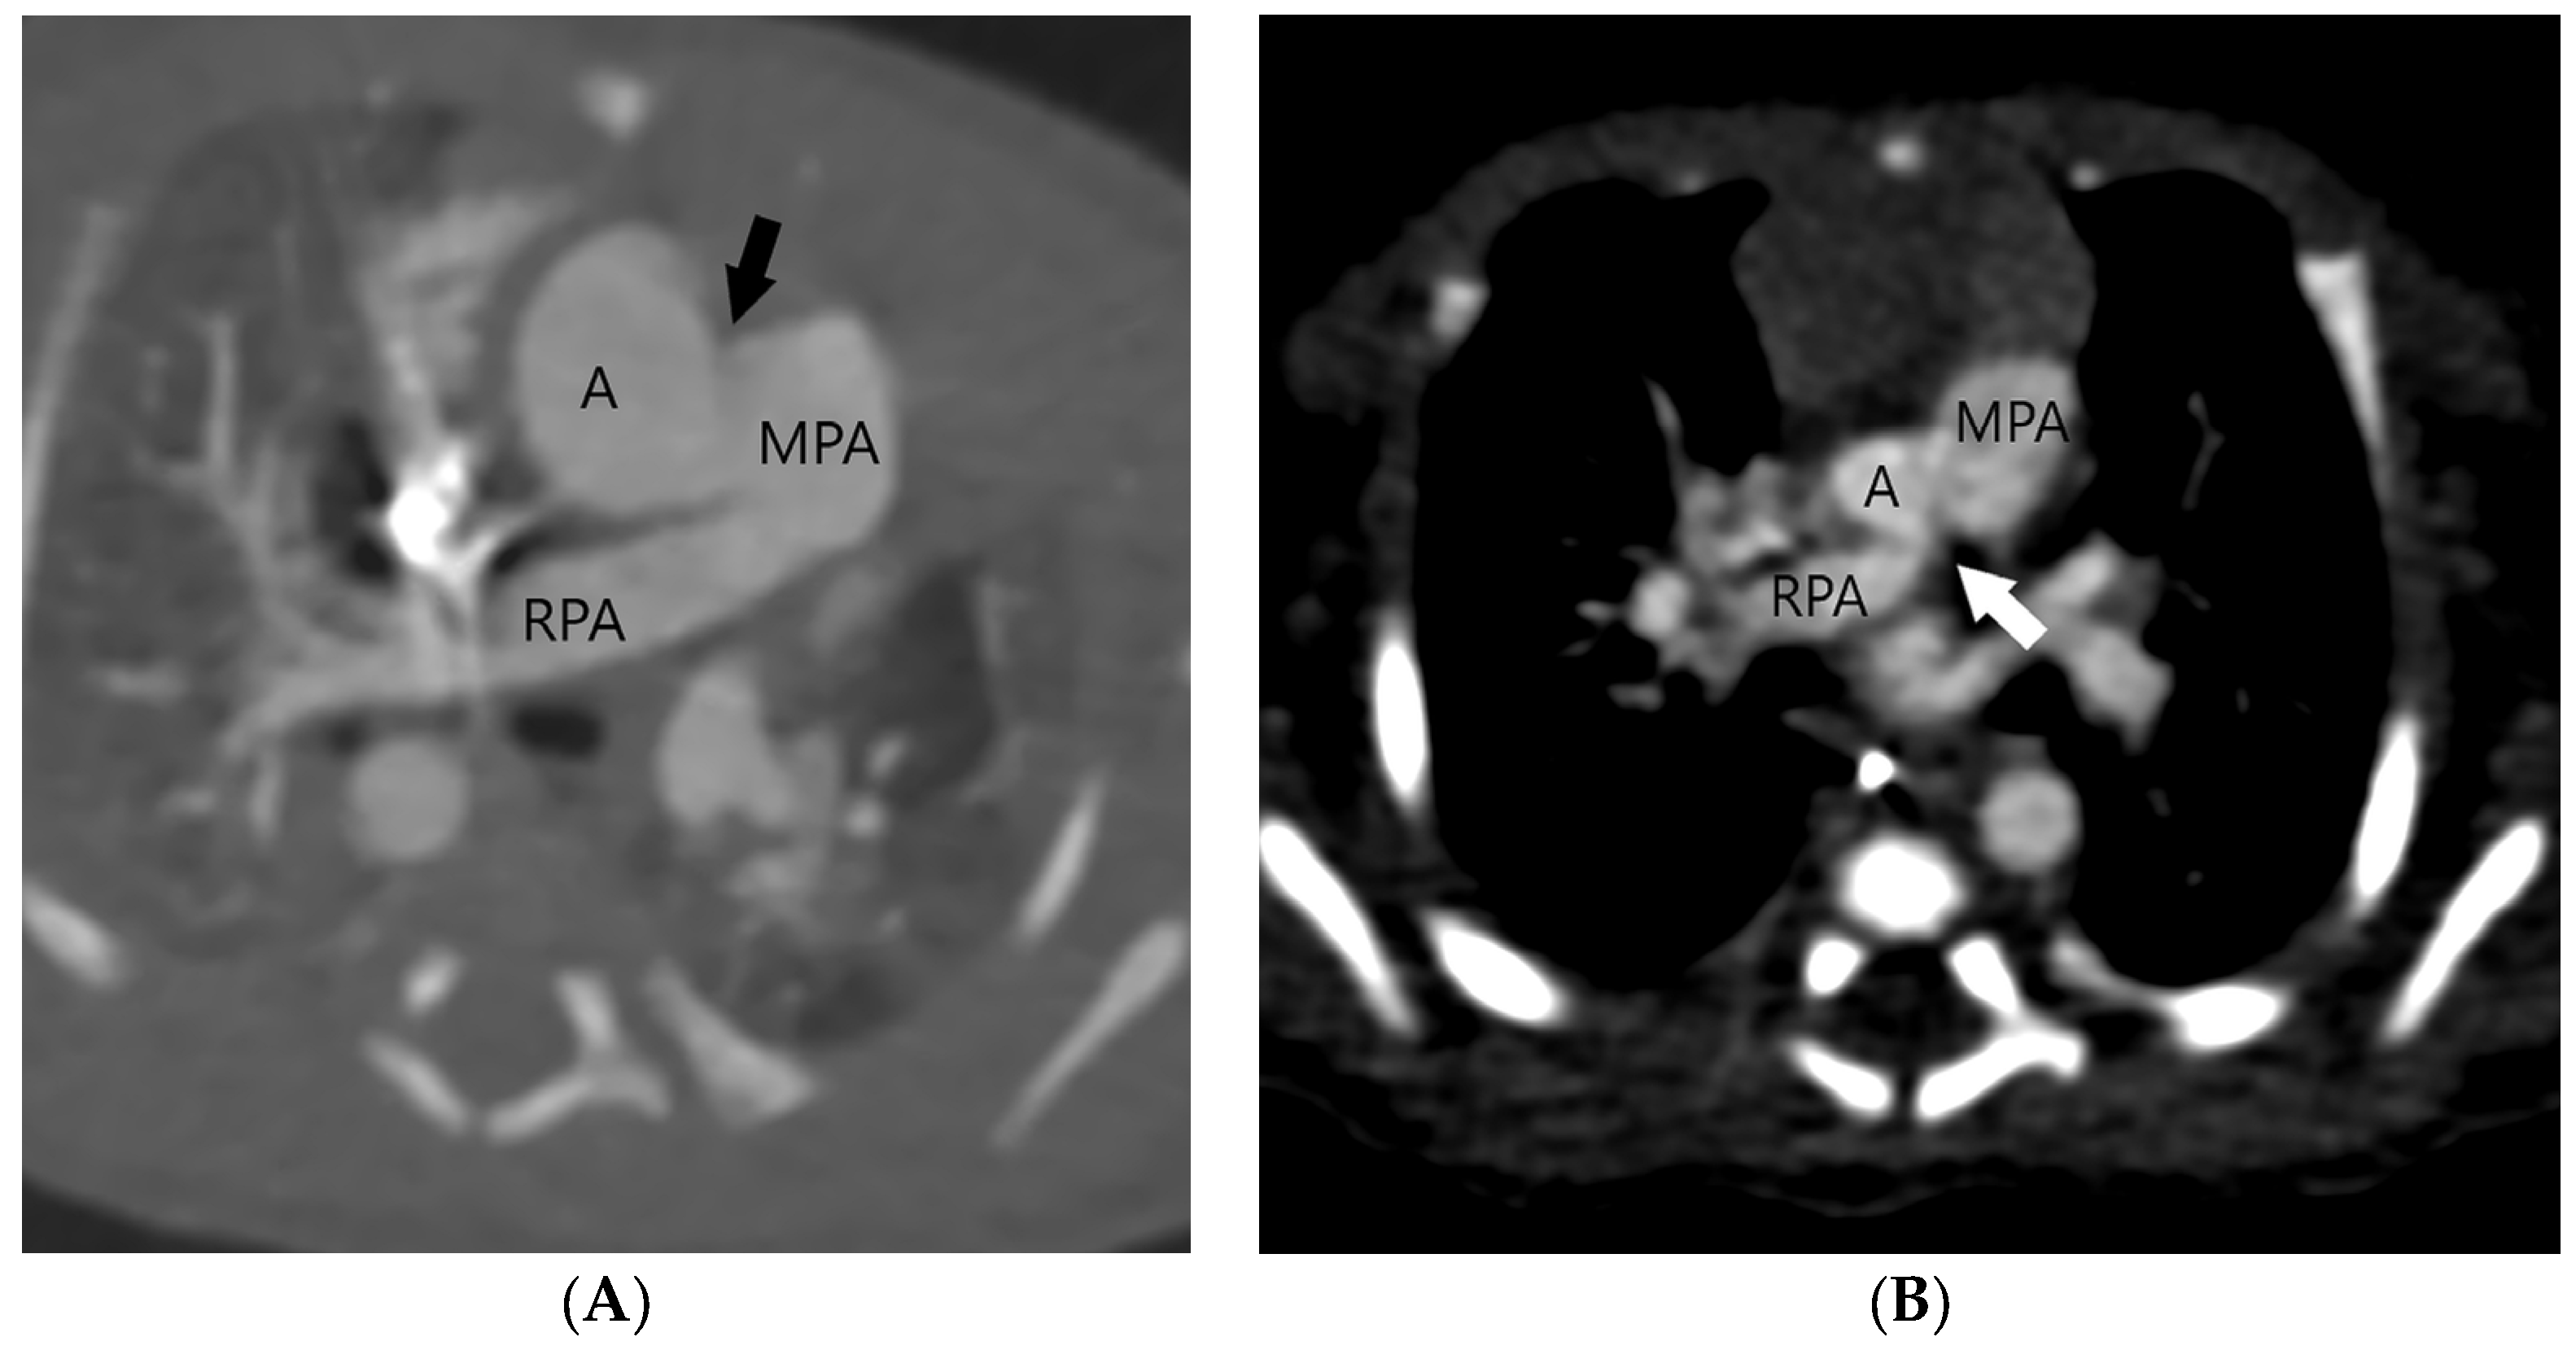

The aortopulmonary septal defect is located between the semilunar valves and the branch pulmonary arteries. If an APW is identified on CT, its type should be determined. Type 1 or (Figure 2) Type 2 APW is located between the distal part of the ascending aorta and the anterior wall of the origin of the right pulmonary artery (Figure 3), whereas type 3 is a total defect that involves the entire aortopulmonary septum or ascending aorta [1]. Type 4 or an intermediate type has similar features to the total defect but has adequate superior and inferior rims and is most suited for device closure [1]. Table 1 summarizes key points in the CT evaluation of patients with an aortopulmonary window.

Figure 2.

Type 1 or proximal type of aortopulmonary septal defect (arrow) is located just above the semilunar valve between the ascending aorta (A) and the right wall of the main pulmonary artery (MPA) (A). The right-sided aortic arch can also be detected. After surgery, the ascending aorta (A) and the main pulmonary artery (MPA) are separated (B).

Precise planning of APW closure is required, since an iatrogenic anomalous origin of the right pulmonary artery from the aorta after APW ligation has been described [30]. Other possible complications include a residual aortopulmonary septal defect, recurrent laryngeal nerve injury with hoarseness or choking during feeding, and postoperative stenosis of the ascending aorta or the main or branch pulmonary arteries [5,31]. The pulmonary artery or aortic stenosis may be treated by balloon angioplasty or stent implantation if needed. In the case of balloon angioplasty, the procedure should be cautiously performed since an AP window can theoretically recur with aggressive angioplasty. If a complication is suspected or if the evaluation of additional cardiovascular anomalies is required, a CT scan may be repeated after APW repair. The normal postsurgical finding includes a complete separation of the ascending aorta from the main pulmonary artery (Figure 2B).